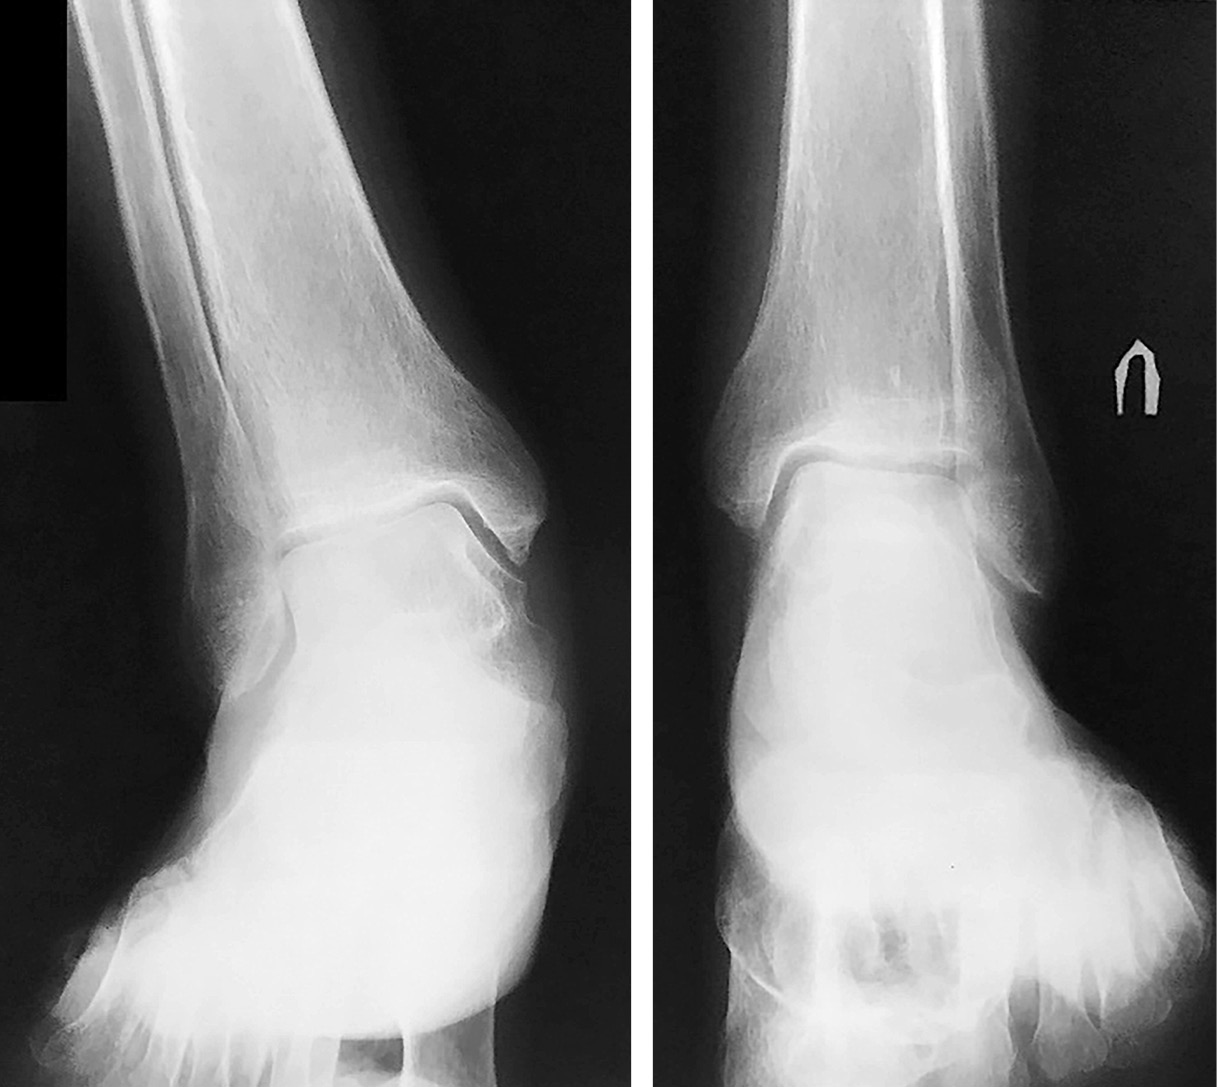

С 2004 г. на рентгенограммах голеностопных суставов – выраженный грубый остеопороз, в области латеральных лодыжек – зоны Лоозера. Имеется дугообразная деформация плюсневых костей. Головка левой плюсневой кости утолщена, имеет остеопоретически-остеосклеротическую метаплазию костных балок с периостальными и параоссальными наслоениями. В мягких тканях IV стадия кальцификации (рис. 3).

Рис. 3. Рентгенограммы голеностопных суставов, 2004 г.